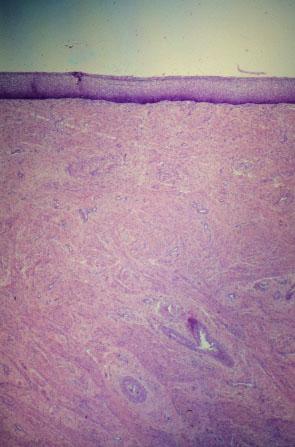

II-21 (4) Slide 104, Vagina (H&E). Low power view. Epithelium is at the top.